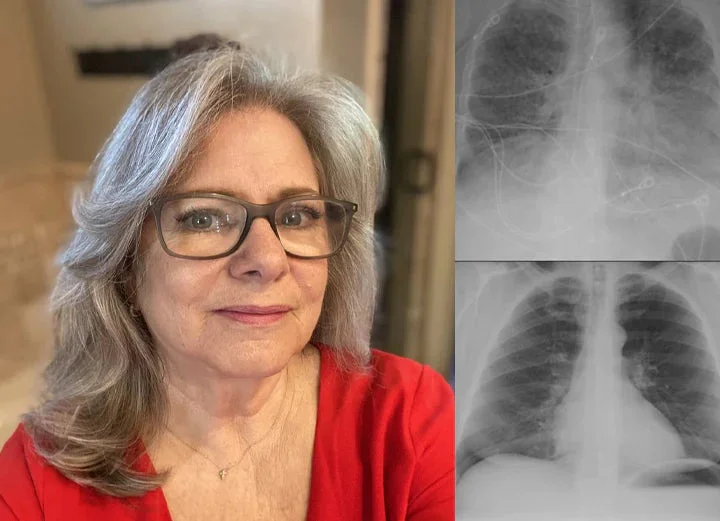

“Living in a polluted city, I battled constant wheezing and exhaustion for years. Medications helped but made me feel drained. With BQYOOM™ Breatheora nasal inhalation, I felt my airways open up within 2 minutes of first use! My cough disappeared within two weeks, and breathing became much smoother. The instant relief is incredible.“

— Linda M., Age 52, ⭐⭐⭐⭐⭐